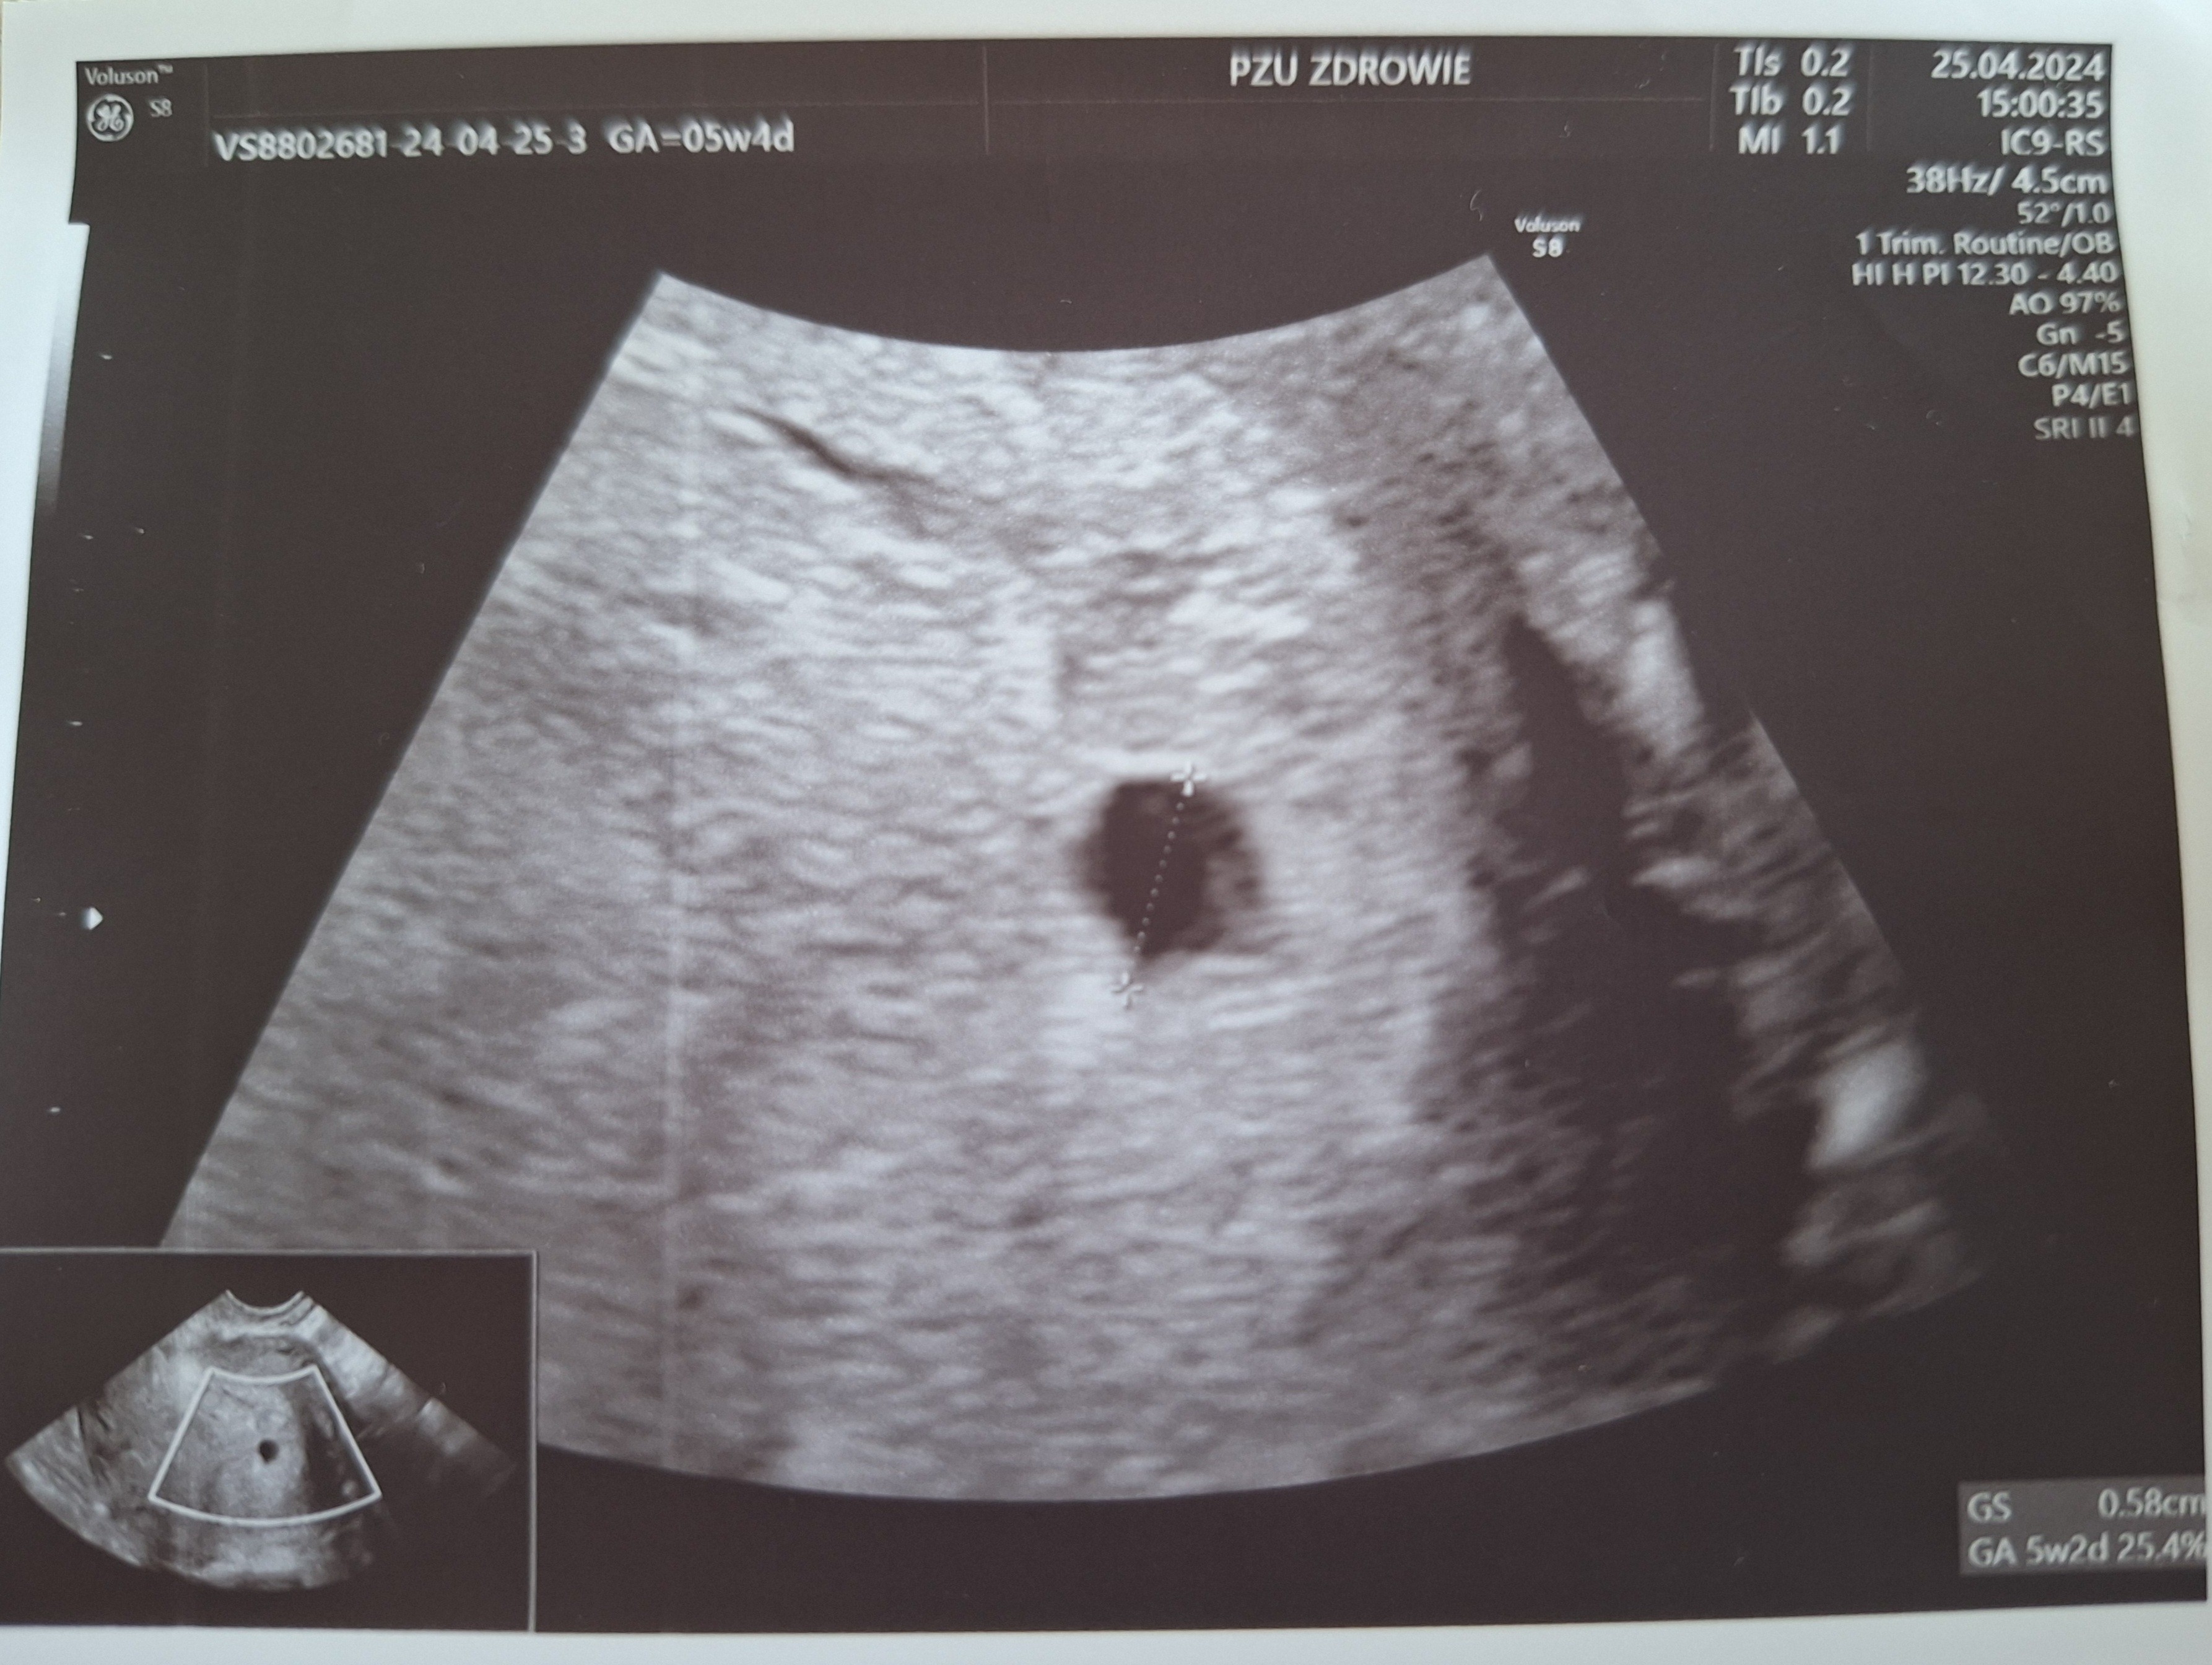

Kolejna beta po tej 234 po 48h była 490 i następna po 72h 1540. U mojego gina w zeszły czwartek był ten duży pęcherzyk, który widoczny był na pzu we wtorek plus obok drugi malutki. Dostałam luteinę ze względu na stan po cc, zlecenie podstawowych badań i kolejna wizyta 6.05. Oczywiście to strasznie długo 😉 więc byłam wczoraj znów na pzu. Jest pecherzyk wielkości 5+2 z widocznym polem zarodkowym(?) Taki słaby cień w środku był widoczny. No i nadal nie wiem, czy to ten pierwszy z zeszłego wtorku się nie zmienił (wtedy był wielkości właśnie ok 5 tc), czy to ten drugi malutki urósł jak powinien a ten pierwszy zniknął... Tyle z moich usg I bety😉

Czekam zatem do tego 6.05 i zobaczymy. Pocieszam się, że wczoraj gin z pzu powiedział, że mam "bardzo ładny pecherzyk ciążowy"🤷‍♀️

Po ostatniej wizycie na PZU w zeszły czwartek (wg mnie 5+3) był widoczny pecherzyk 5+2 (więc niby okej, jeden dzień różnicy), ale bez widocznego pęcherzyka żółtkowego i zarodka. Lekarz kazał przyjść za tydzień, ale ponieważ gabinety zamknięte, bo majówka, to byłam wczoraj, we wtorek, wg mnie to było 6+1. Na USG widoczny pęcherzyk ciążowy 1,01 cm 5+5 ( czyli 3 dni różnicy z wymiaru) z pęcherzykiem żółtkowym 0,51 mm... zarodka nie widać. Niby w jednym miejscu lekarz pokazywał, że tam może być zarodek, no ale nie było co mierzyć, bo za małe. Czy dobrze myślę, że ten pęcherzyk żółtkowy jest za duży jak na taki wiek ciąży i na taki rozmiar pęcherzyka ciążowego? Jeszcze myślę, że może kiepskie ujęcie, bo ścianki YS są mocno pogrubione a zmierzone jakby po zewnętrznej, ale mimo wszystko, w czwartek nie było w środku nic a po 5 dniach nagle taki duży YS? Lekarz był bardzo młody, jeszcze chyba w trakcie specjalizacji, bardzo się starał i był uważny, ale chyba trochę popłynął mówiąc, że pecherzyk żółtkowy o wymiarach połowy pęcherzyka ciążowego to dobry znak... Co sądzicie?